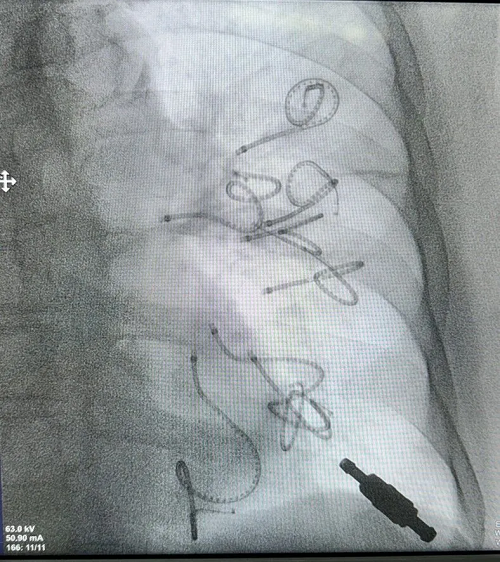

图3:术中影像:左肺共置入8枚回力圈